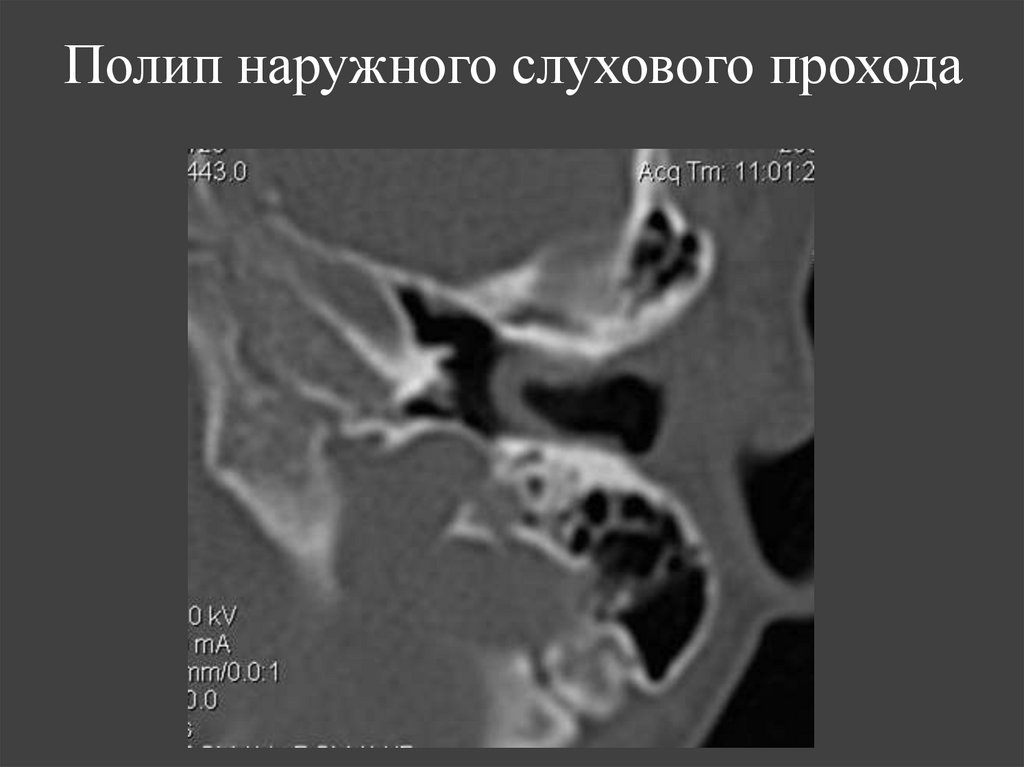

72. Полип наружного слухового прохода